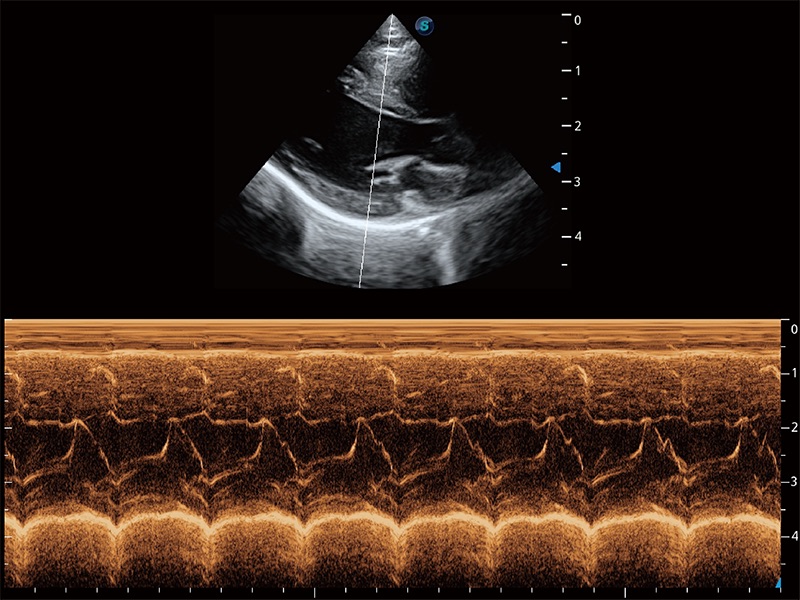

(猫)二尖瓣M型

• AMM 解剖M型

通过360度任意调节3条M型取样线,在同一心动周期上观察心脏不同位置的运动曲线,得到准确的心功能测量数据,有效评估心肌运动及左心室功能。